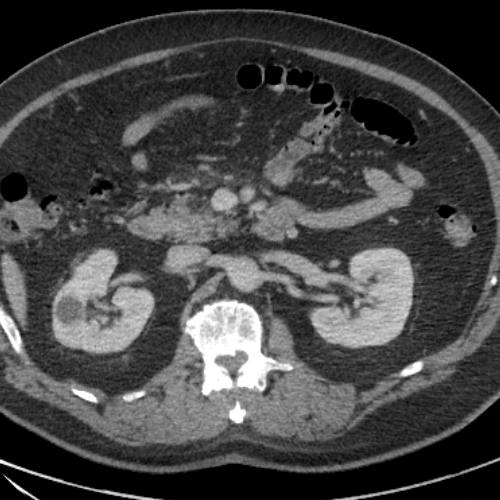

CaseStacks.com — Case #74 — Meckel Diverticulitis

CaseStacks.com — Case #74 — Meckel diverticulitis www.casestacks.com

casestacks diverticulitis meckel ct